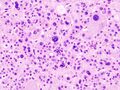

علم الانسجة

يشير تحليل النسيجي المرضي المجهري لعينات الأنسجة التي تم الحصول عليها من قشرة الغدة الكظرية للأفراد الذين يعانون من أعراض مرتبطة بالورم الغدي مثل الالدوسترونية الأولية (PA) إلى أن خلايا الورم الغدي أكبر نسبيًا مع اختلاف السيتوبلازم ، وزيادة التباين في الحجم النووي. يعتمد هذا المؤشر على المقارنة بين عينات أنسجة قشرة الغدة الكظرية السليمة (الطبيعية) والمتأثرة (المرتبطة بالورم الغدي).[بحاجة لمصدر]

يتم تمييز أورام الغدة الكظرية الغدية الأكثر شيوعًا عن سرطان القشرة الكظرية (نظائرها الخبيثة) بواسطة نظام فايس,[11] علي النحو التالي::[12]

| الخصائص[12] | النتيجة |

|---|---|

| درجة نووية عالية (مكبرة ، بيضاوية إلى مفصصة ، ذات حبيبات خشنة إلى كروماتين مفرط اللون ويمكن تمييزها بسهولة ، نوى بارزة))[13] | 1 |

| انقسامات فتيلية أكثر من 5/50 حقول طاقة عالية | 1 |

| انقسامات فتيلية شاذة | 1 |

| السيتوبلازم اليوزيني في> 75٪ من الخلايا السرطانية | 1 |

| بنية منتشرة تزيد عن 33٪ من الورم | 1 |

| نخر | 1 |

| الغزو الوريدي | 1 |

| الغزو الجيبي (لا توجد عضلات ملساء في الجدار) | 1 |

| غزو المحفظة | 1 |

تشير النتيجة الإجمالية إلى:[12]

- 0-2: ورم الغدة الكظرية الغدية

- 3: غير محدد

- 4-9: سرطان القشرة الكظرية